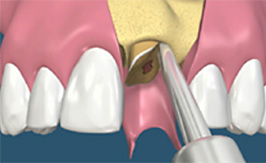

[치아발치]